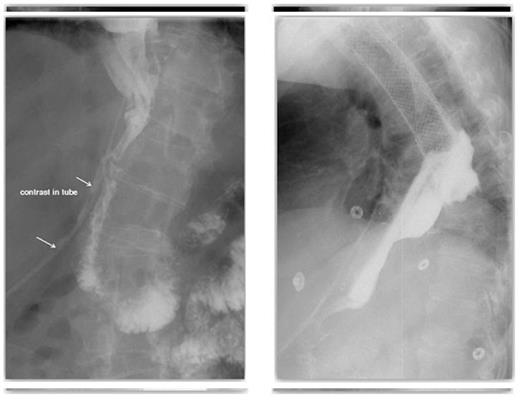

A novel approach to the management of a fistula after pyloroplasty was employed. A combined endoscopic and fluoroscopic procedure was performed where a radiologically placed snare was inserted through the abdominal drain and manipulated into the gastric tube through the defect in the pyloroplasty. A gastroscope was used to introduce a T-tube into the gastric tube and into the snare. The abdominal drain and snare were withdrawn and the T-tube placed appropriately, plugging the hole in the pyloroplasty, under direct vision. A further guide wire was left in place along the tract of the tube drain and was used to deploy a pigtail drain alongside the pyloroplasty (Figures 5 and 6).

An Intra-operative image demonstrating the combined endoscopic and fluoroscopic procedure